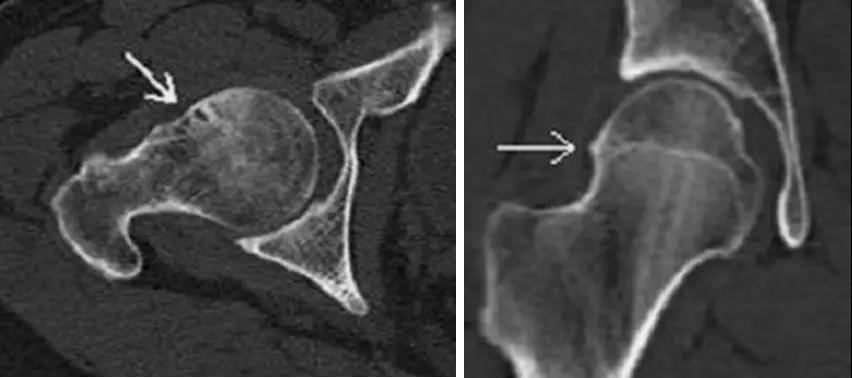

凸轮撞击型FAI▼

- 股骨头颈联合处前上缘骨性突起。

- 非圆形的股骨头。

- 股骨头颈联合处前缘骨性突起、骨质硬化,α角增大。

钳夹撞击型FAI▼